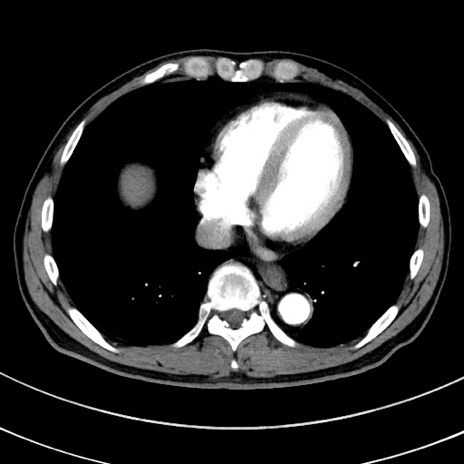

症例8(横断像)

【症例】 60歳代男性

【主訴】 黒色吐物

【現病歴】 4日前から嘔気自覚、2日前の朝食後にも嘔気あり、自分で手で嘔吐反射起こし嘔吐したところ血が混ざっていたため受診。

【既往歴】 5年前汎発性腹膜炎を伴う急性虫垂炎で手術、高血圧、前立腺肥大症、高脂血症

【身体所見】 腹部正中に手術癩痕あり 腹部平坦・軟圧痛なし膨満感あり

【データ】WBC 8400、CRP 4.54